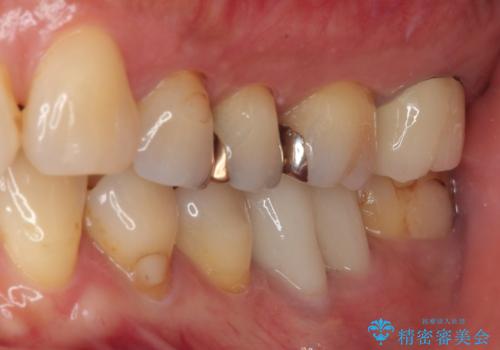

被せものに穴が開いたのでやり替えたい オールセラミッククラウン

- 被せものに穴が開いたとのことで来院された患者様です。被せものをやり替えることになったので、かみ合わせが強い方のでPGAクラウンをご提案しましたが患者様の強いご希望によりオールセラミッククラウンによる補綴治療を行っていくことになりました。

拡大鏡視野下で、金属の被せもの、虫歯の除去を行い、オールセラミッククラウンに適した形に整えました。

機能面、見た目共に満足していただきました。今後はメンテナンスで通っていただく予定です。

咬み合わせが強い方なので就寝時ナイトガードを使ってもらいます。